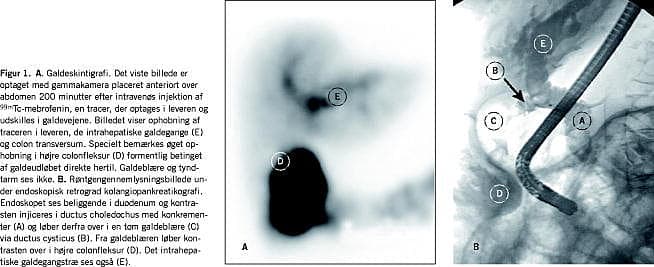

Ved en ultralydundersøgelse (UL) af abdomen blev der fundet luft i galdevejene. En efterfølgende koleskintigrafi viste en fistel fra galdeblæren til højre colonfleksur (Figur 1A). Ved en endoskopisk retrograd kolangiopankreatikografi (ERCP) blev der fundet sten i ductus choledochus og kontrastoverløb fra galdeblæren til colon (Figur 1B). Der blev udført sfinkterotomi og stenfjernelse fra ductus choleodocus. Man afstod fra kolecystektomi på grund af patientens alder.

Fistler fra galdeblæren til colon (FGK) diagnosticeres sjældent. Vi beretter om en patient med atypiske symptomer på en FGK. En 93-årig kvinde blev henvist på grund af vægttab og diare. I fæcesprøver blev der påvist steatorré, og denne forsvandt ved substitution med pancreasenzymer. En ultralydundersøgelse af abdomen viste luft i galdeblæren og en kolocystografi med technetium 99m bekræftede hypotesen om FGK. Kvinden blev behandlet med papillektomi ved endoskopisk retrograd i kolangiopankreatografi, hvorved sten i galdegangen blev fjernet, og passagen i galdegangen blev reetableret.